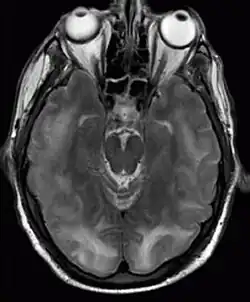

Die eingangs meist durchgeführte Computertomografie bleibt in mindestens der Hälfte der Erkrankten ohne richtungsweisenden Befund. In der Kernspintomografie des Kopfes lässt sich das meist ausgeprägte Ödem (vor allem in der FLAIR- oder T2-Wichtung) gut darstellen. Seltener tritt das Hirnödem betont in den seitlichen oder vorderen Hirnteilen oder im Hirnstamm auf.[2] Der Nachweis von Komplikationen (Diffusionsstörungen, Blutungen) spricht für einen ungünstigeren Krankheitsverlauf. Im Nervenwasser wird oft eine Vermehrung des Protein nachgewiesen, jedoch keine relevante Zellzahlerhöhung. Im EEG findet sich eine Allgemeinveränderung, entsprechend dem klinischen Verlauf können epilepsietypische Zeichen nachweisbar sein. Sofern eine Gefäßdarstellung mit Kontrastmittel durchgeführt wird, finden sich meist lokal begrenzte Erweiterungen und Verengungen der hirnversorgenden Arterien, besonders der A. cerebri posterior.[1]